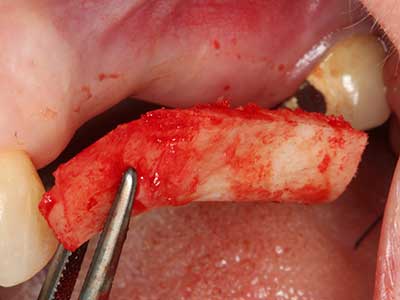

Autologous bone transplants are used in the form of blocks, shells, rings and are also combined with bone replacement materials as chips. If the implant site is prepared at the same time as the augmentation, various bone filter systems have proven effective for collecting the resulting bone chips. As an alternative, the implant site can be prepared using a low-speed device without irrigation. If an implant is not inserted, bone chips can be harvested from the periphery with bone scrapers. This is also possible with piezosurgery using specialized attachments that yield higher-quality bone chips compared chips harvested with round drills, as has been confirmed in a study comparing the two methods (Chiriac, Herten et al. 2005).

Piezosurgery has additional advantages when harvesting bone blocks. In addition to the high precision with osteotomy described above, the use of the thin saw tips specifically minimizes loss of material. Greater loss of material during harvesting can be expected with the thicker instrument tips, particularly when using Lindemann drills (Lakshmiganthan, Gokulanathan et al. 2012). The basal separation, which is necessary particularly for retromolar block transplants, is simplified by specially designed rectangular saws, with the result that piezosurgery is viewed as a precise, simple and safe procedure for harvesting retromolar bone blocks (Happe 2007) (Fig. 1-12).